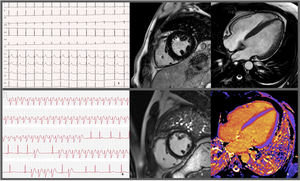

Electrocardiograms and cardiac magnetic resonance imaging exams performed on the patient. 1: EKG performed prior to hospitalization discharge showing no remarkable findings other than an rSr’ pattern in lead DIII. 2 and 3: MRI prior to hospitalization discharge revealing slight concentric hypertrophy, without enhancement. 4: Recording of a wide QRS tachycardia, raising the hypothesis/possibility of a non-sustained ventricular tachycardia. 5 and 6: MRI during follow-up, showing absence of LGE and normal native T1 mapping values (considering the reference values for the sequence and local MRI laboratory).

A 25-year-old male with no significant medical or family history presented with fever, tonsillitis, and rapidly progressing dyspnea, leading to respiratory failure and intubation. Initial tests showed elevated creatinine kinase (CK) levels (1200 U/L, normal <189 U/L) and myoglobinuria, requiring transitional renal replacement therapy. Echocardiogram revealed moderately reduced left ventricular ejection fraction (LVEF 45%). Myocarditis was suspected, but cardiac magnetic resonance imaging (MRI) performed 10 days later showed LVEF recovery and mild hypertrophy (13 mm), without edema or fibrosis; serum troponin T was only mildly increased (peak 70 ng/L, N <14 ng/L) (Figure 1). The episode was attributed to a systemic viral syndrome with multiorgan involvement.

The patient remained stable with normal LVEF over three years and was discharged. However, at age 30, he returned with palpitations and brief tachycardia episodes were detected by his smartwatch. An MRI during follow-up revealed a decrease in left ventricular wall thickness and right ventricular dilation compared to the previous MRI, without late gadolinium enhancement and normal T1 mapping (Figure 1).